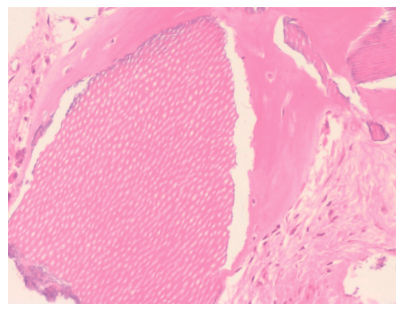

La muestra tomada se envió a analizar al Servicio Diagnóstico de Patología Oral y Maxilofacial del Dr. Aguirre en Vizcaya. El resultado de la biopsia describe “tejido óseo trabecular vital. Se observan múltiples fragmentos irregulares de dentina tubular, reconociéndose neoformación ósea en íntimo contacto de algunos de ellos”, además de aportar cortes microscópicos (Figura 12). Debido a que se observó una zona con una densidad muy baja, se recomendó la re-entrada a los 6 meses para evaluar la calidad del hueso regenerado con dentina.